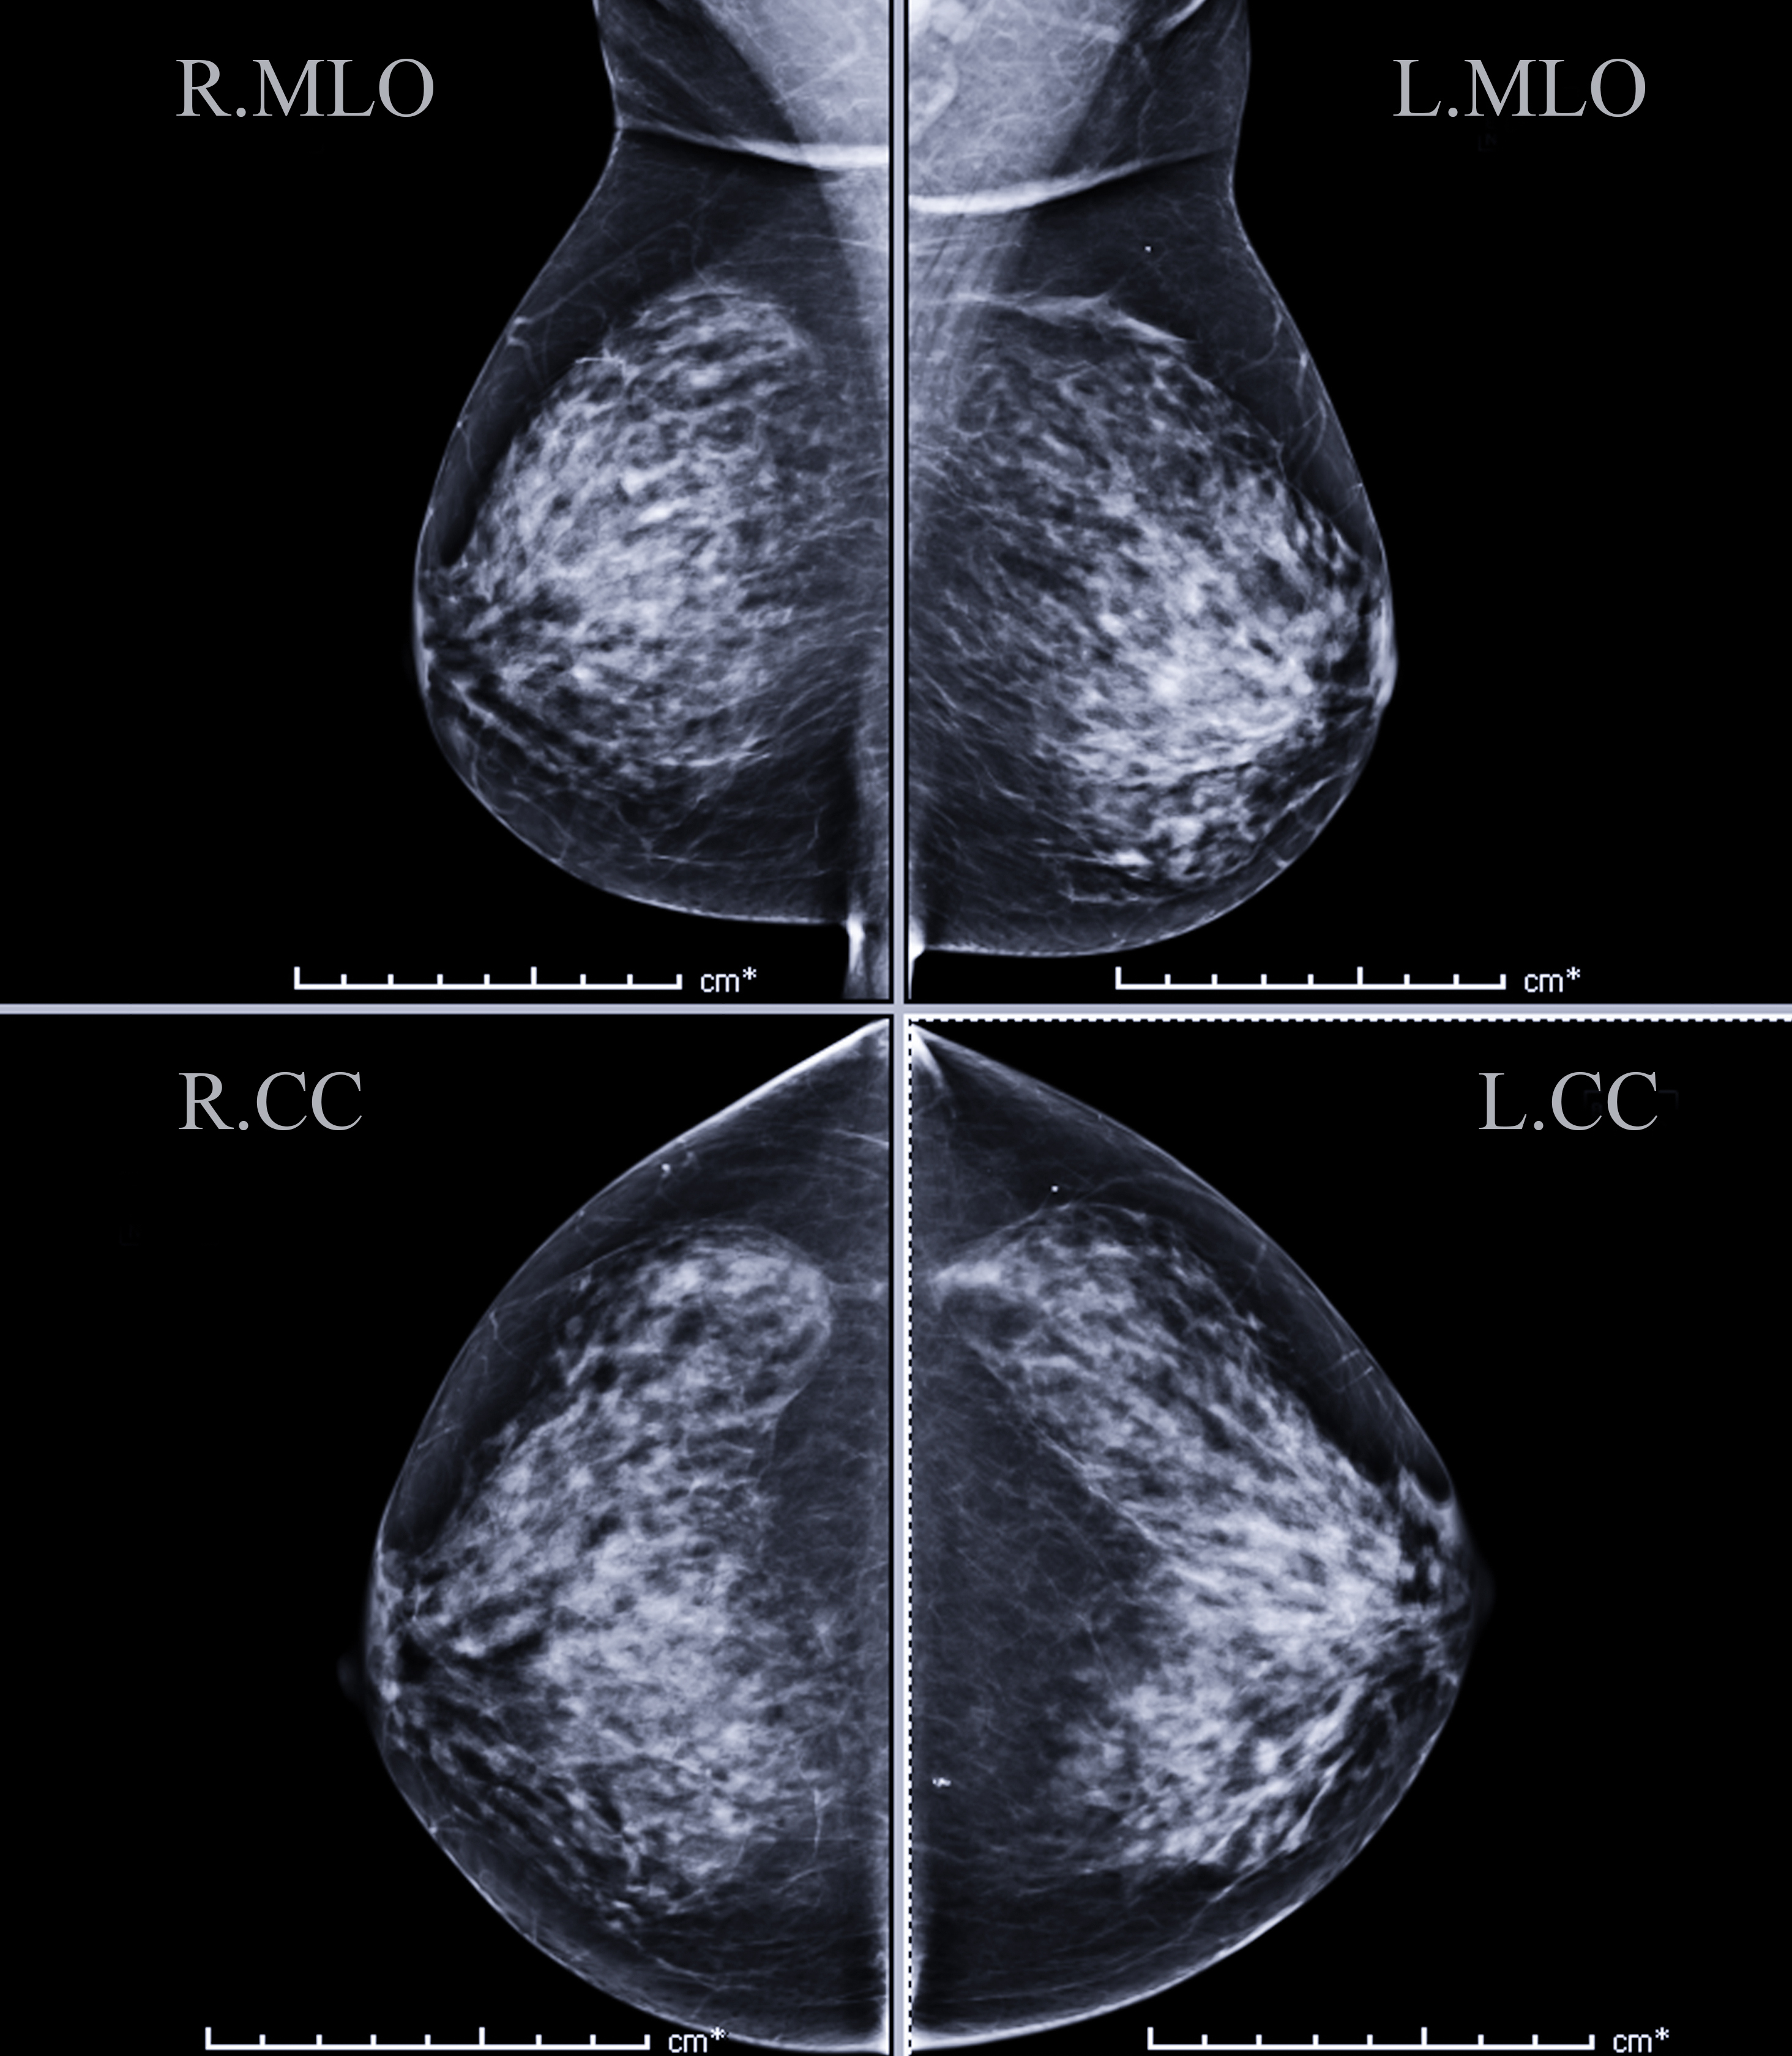

Breast Cancer Screening

Individualizing breast cancer screening recommendations involves tailoring screening guidelines to the specific needs and risk factors of each individual. Traditional screening guidelines often follow a one-size-fits-all approach, recommending mammograms at a certain age and frequency for all women. However, individualizing recommendations takes into account factors such as family history, genetic predisposition, personal health history, breast density, and lifestyle factors to create a personalized screening plan. For example, women with a family history of breast cancer or certain genetic mutations may benefit from an annual breast MRI, while women with dense breasts may need an annual breast ultrasound.

Advancements in technology and understanding of breast cancer risk have enabled healthcare providers to offer more personalized screening recommendations. Tools such as risk assessment models and genetic testing can help identify individuals at higher risk for developing breast cancer, allowing for earlier detection and intervention. Additionally, factors such as breast density and hormonal factors can also influence screening recommendations, highlighting the importance of considering a comprehensive range of factors when developing an individualized screening plan.